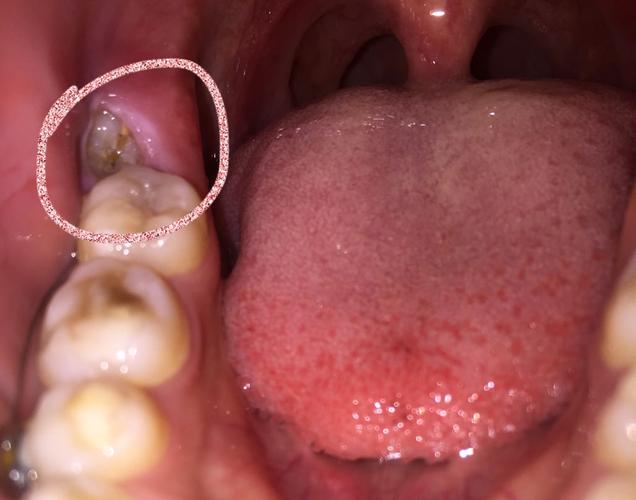

智齿包在肉里面怎么办

智齿包在肉里面怎么办,智齿包在肉里面

智齿包在肉里面

智齿包在肉里面图片

智齿半包在肉里面图片

智齿长出一半被肉包着

肉包智齿图片

牙齿被肉包住了图片

尽头牙长肉包裹图片

智齿露一半包一半图